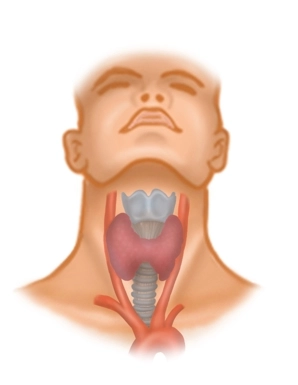

Situado entre el borde anterior del M. sternocleidomastoideus, la mandíbula y la fosa yugular, el triángulo cervical anterior en la zona del hueso hioides contiene la musculatura supra- e infrahioidea, vasos, nervios y la glándula tiroides. Para la tiroidectomía, de los músculos infrahioideos posiblemente el situado medialmente

son de importancia, ya que cubren parcialmente la glándula tiroides y deben ser desplazados lateralmente de forma intraoperatoria.